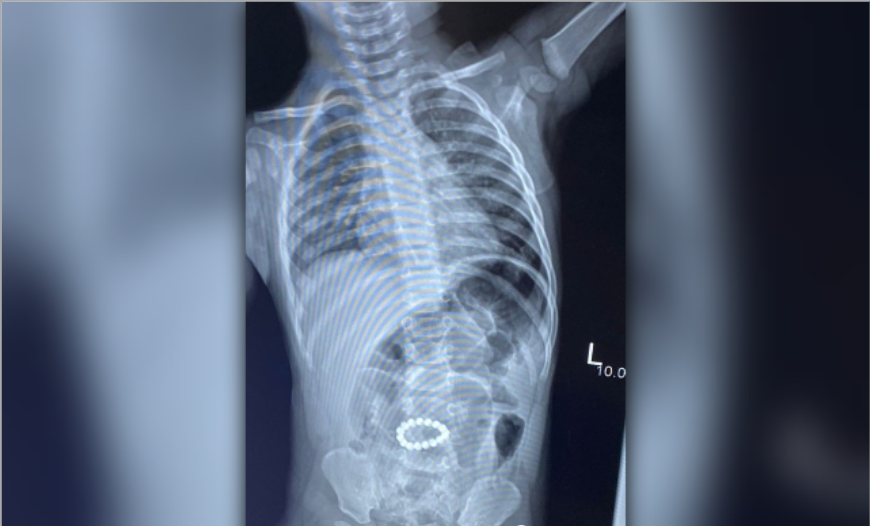

Рентген показал 16 магнитов, которые, соединившись между собой в кольцо, находились в брюшной полости. Они спаяли петли кишечника, вызвали некроз и через перфорации вышли в брюшную полость, вызывая признаки перитонита.